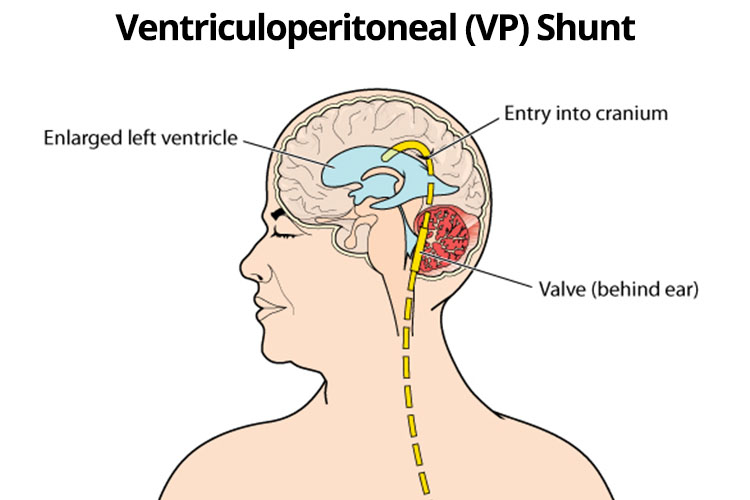

Вентрикуло-перитонеальный шунт: Показания и применение

Раздел: Фотоальбом решений